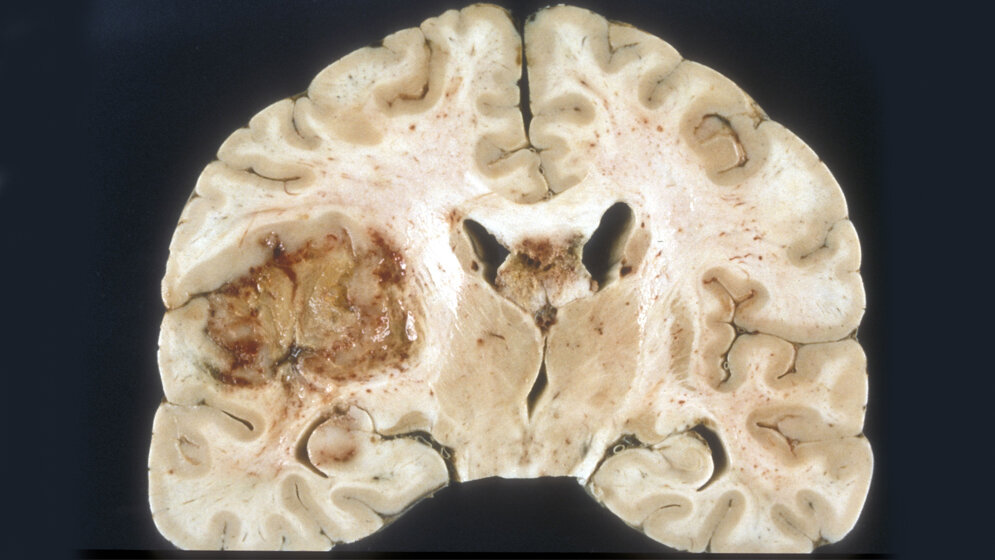

Schnelles Wachstum, starke Infiltration des umliegenden Gewebes und häufige Rückkehr auch nach erfolgreicher Therapie innerhalb weniger Monate: Das sind die Kennzeichen des sogenannten Glioblastoms. Der Tumor entwickelt sich aus dem Stützgewebe des Gehirns, den Gliazellen; er zählt zu den häufigsten Hirntumoren bei Erwachsenen. Das Glioblastoma multiforme ist die aggressivste Variante dieser Krebsart.

Erste Symptome sind die klassischen Anzeichen eines erhöhten Hirndrucks wie etwa Kopfschmerzen, Schwindel und Erbrechen. Später leiden die Erkrankten häufig unter neurologischen Ausfällen, zu denen Seh- und Sprachstörungen sowie Lähmungserscheinungen gehören, aber auch epileptische Anfälle und psychische Veränderungen.

Die Standardbehandlung besteht aktuell aus den drei Bausteinen Operation, Bestrahlung und Chemotherapie. Der Erfolg dieser Maßnahmen ist begrenzt: Ein Jahr nach der Diagnose sind maximal 50 Prozent der Betroffenen, nach zwei Jahren nur noch zehn bis 15 Prozent am Leben; die mittlere Überlebenszeit liegt bei etwa 15 Monaten.